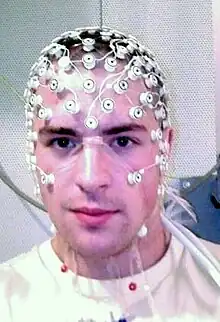

Seizures often begin when patients are young, although studies have shown adult onset as well. Many causes of the epilepsy have been theorized, with EEG often finding the hamartoma itself as the source of electrical activity, or epileptogenic focus. With chronic seizures, cognitive decline can develop, which can manifest as poor school performance, decreased nervous stimulus IQ, or limited socialization. Other symptoms of this tumor type include visual disturbances, such as the appearance of motion from a stationary object, or inappropriate color perception of the entire visual field.[6]

Surgery is offered if there is failure of medical therapy or rapid growth of lesion, with specific options including stereotactic thermocoagulation, gamma knife radiosurgery, and physical resection by transsphenoidal microsurgery. Surgical response is typically better when the seizure focus has been found by EEG to originate in or near the mass. The specific location of the lesion relative to the pituitary and infundibulum and the amount of hormonal disturbance at presentation can help predict risk of hypopituitarism following surgery.[8]